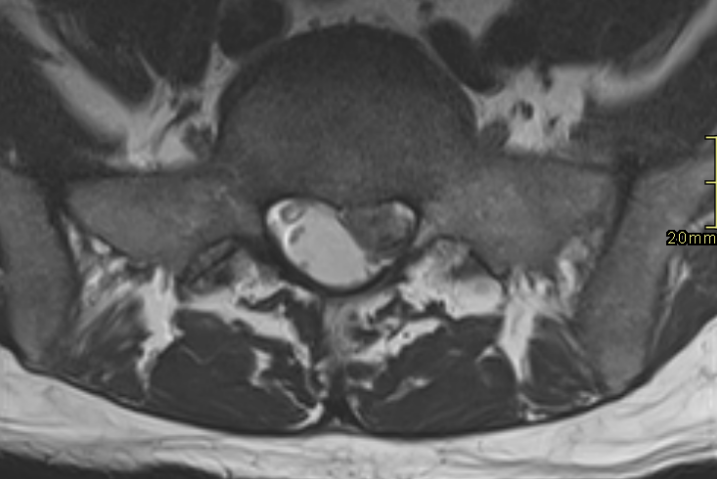

Left S1 nerve compression due to extruded disc